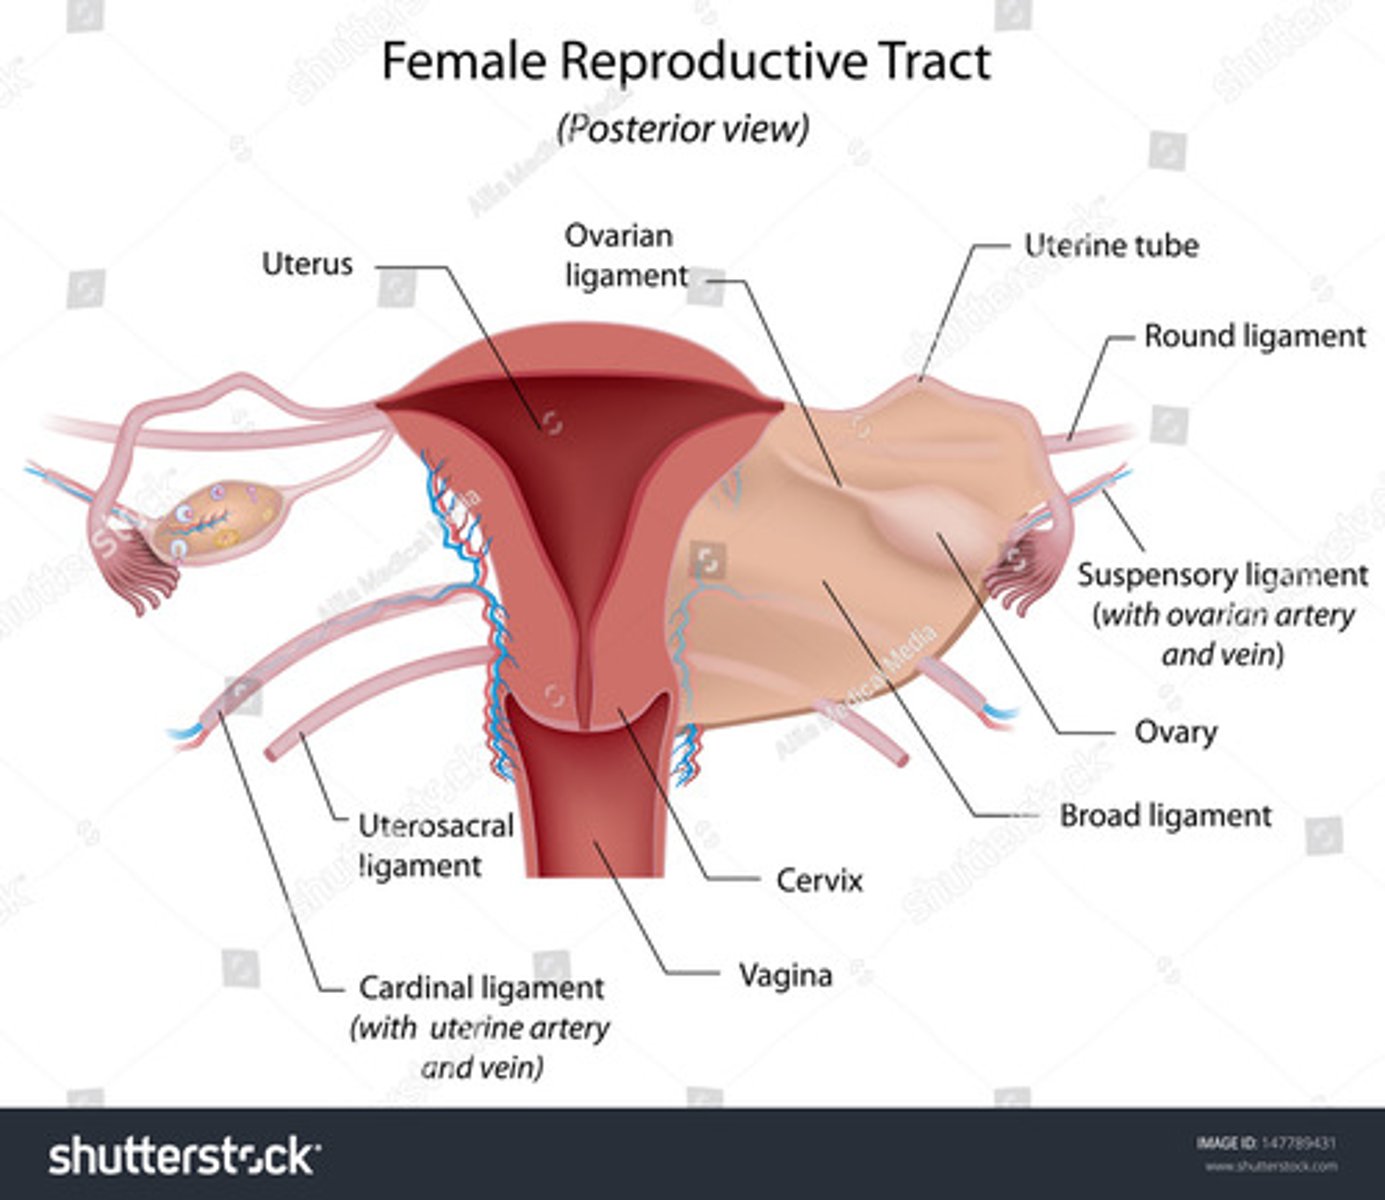

The broad ligaments extend between the ___ and ___

uterine body; ovary

What is positioned between the 2 layers of the broad ligaments?

fallopian tubes

round ligament

ovarian ligament vascular structures

The round ligaments are located ___ to the fallopian tubes and insert into the ___ to help maintain the ___ of the uterus

anteroinferior; labia majora; position

The ovarian ligaments are located ___ at the ___ of the uterus

bilaterally; cornua

The suspensory ligaments extend from the ___ to the ___

infundibulum; pelvic sidewall